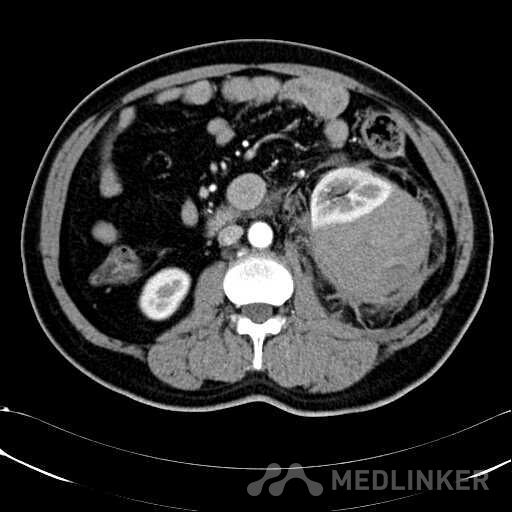

患者是54岁男性 主 诉: 突发左腰部疼痛3小时。 现病史: 缘于入院前3小时患者无明显诱因出现左腰部剧烈疼痛,无向他处放射,与活动及体位无明显关系,伴有腹胀、恶心、呕吐,无头痛、头晕,无人事不省、口吐白沫,无胸闷、胸痛、咯血,无发热、畏冷、寒战,大小便未解,肛门无停止排气,遂就诊我院,查“泌尿系彩超:左肾实质及不均质回声区,范围约9.4*4.1cm,界不清,内未见明显血流信号”,为进一步治疗,门诊拟“左肾占位”收住入院,发病以来,患者精神欠佳,未进食,大小便如前述,体重无明显改变。 患有“高血压病”7年,规则服药治疗(具体不详),监测血压情况不详。 T: 36.5 ℃ P: 65 次/分 R: 20 次/分 BP: 154/94 mmHg 双肾区皮肤无红肿、破溃及隆起,双肾肋下均不能被触及,左侧肾区叩击痛明显,右侧肾区无叩击痛,双侧肾区未闻及血管杂音。膀胱区无隆起,无压痛,耻骨上膀胱区叩诊空虚。外生殖器发育正常。 2016-04-12 泌尿系彩超:左肾实质及不均质回声区,范围约9.4*4.1cm,界不清,内未见明显血流信号。 04-12血常规:血红蛋白 151 g/L,白细胞 16.80 10^9/L,中性粒细胞百分比 84.90 %。急诊生化:白蛋白 39.8 g/L,葡萄糖 9.46 mmol/L。